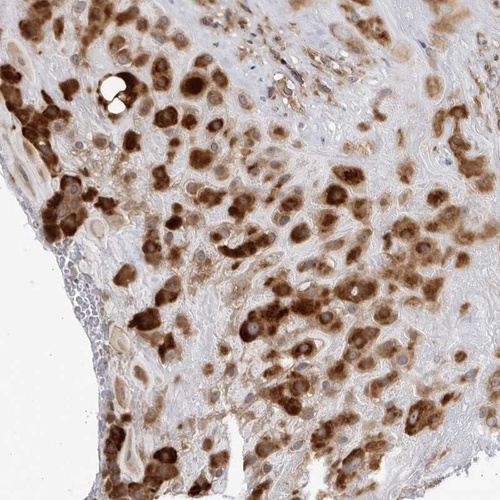

Immunohistochemical staining of human placenta shows strong cytoplasmic positivity in decidual cells.